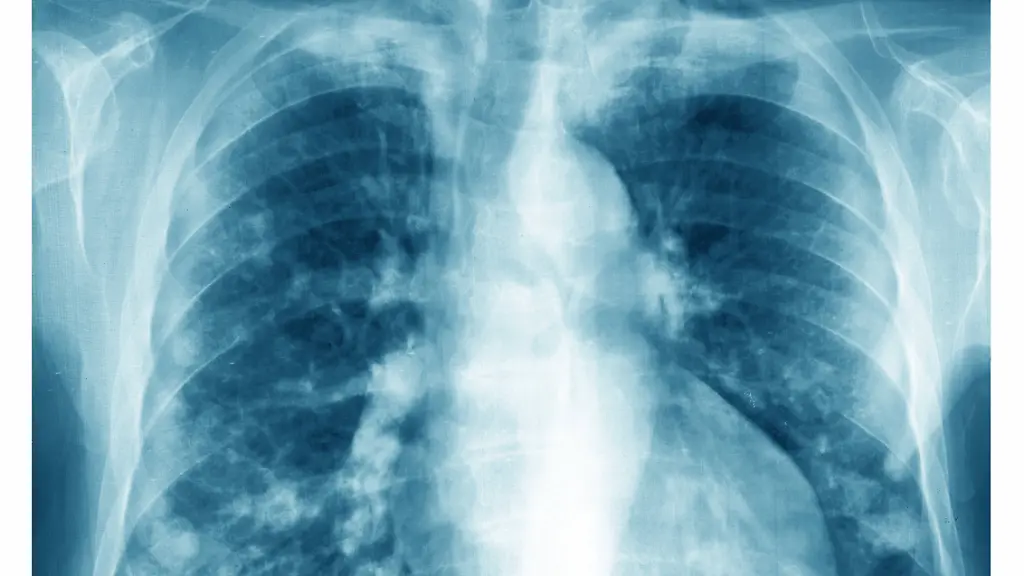

Einsatz fossiler EnergieträgerMögliche Ursache von Lungenkrebs bei Nichtrauchern entdeckt

Die Verbrennung von Kohle, Öl und Benzin schadet nicht nur dem Klima - dabei entstehen auch Abgase, die das Risiko von Lungenkrebs auch bei Nichtrauchern erhöhen. Forschende finden nun heraus, warum das so ist. Und sie entdecken einen möglichen Weg, dem vorzubeugen.